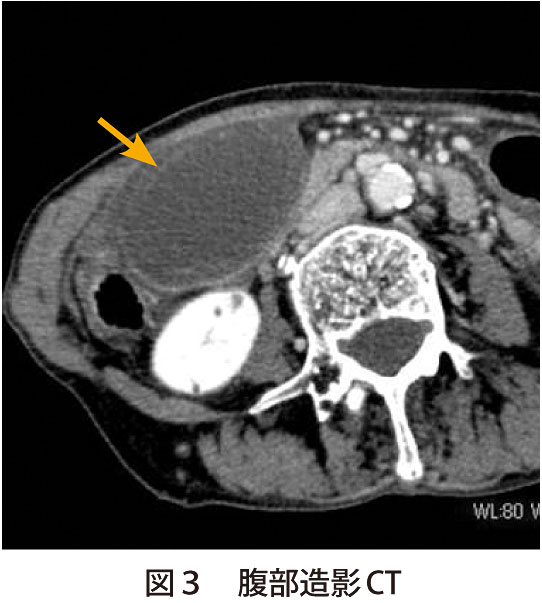

疾患での役割 [ ] 胆石症 [ ] 最大25%の人間が、、、およびで構成されたを持つ。 急性胆のう炎では、胆のうが浮腫などにより肥大しますが、慢性胆のう炎では胆のう壁が分厚くなり、胆のう自体のサイズは萎縮していきます。 写らない場合でも、胆嚢を映し出す造影剤があって、それを経口的、あるいは経静脈的に与えることにより胆嚢を映したり、内視鏡的逆行性胆管造影法によって、中にある石をみつけます。